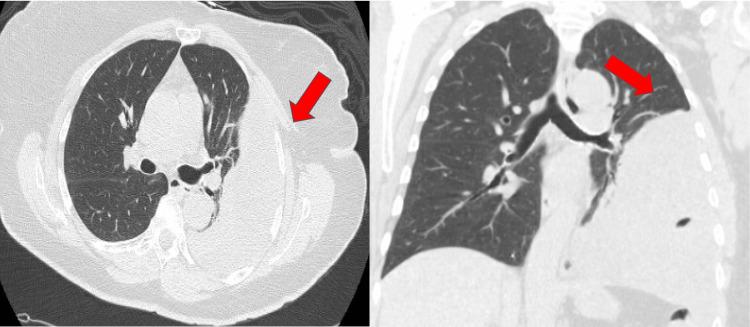

The etiology of complicated pleural effusion can be vast. We present a unique case of an unsuspected metastatic endometrial stromal sarcoma (ESS) in an asymptomatic patient with an incidentally found complicated pleural effusion. A 69-year-old female with no pertinent past medical history was referred to pulmonology for an effusion noted on a routine chest X-ray. Her surgical history was significant for a hysterectomy. At the time of evaluation in the pulmonology clinic, the patient was asymptomatic with stable vital signs. Computed tomography of her chest showed a complex pleural effusion which was drained by cardiothoracic surgery. Fluid analysis results were positive for estrogen and progesterone receptor-positive mesenchymal tumor. Follow-up imaging was negative for any other metastasis. Appropriate management and drainage of this asymptomatic pleural effusion resulted in the diagnosis of a rare malignancy. Given the good clinical prognosis of mesenchymal tumors, the patient was appropriately treated and doing well. We present the case of a patient who was found to have a rare malignancy rather than a benign chronic pleural effusion, as previously suspected. This neoplasm represented a metastatic ESS, especially in this patient's setting of a hysterectomy.

复杂性胸腔积液的病因可能多种多样。我们报告了一例独特的病例,一名无症状患者偶然发现有复杂性胸腔积液,最终确诊为未被怀疑的转移性子宫内膜间质肉瘤(ESS)。一名69岁女性,既往无相关病史,因常规胸部X线检查发现胸腔积液而转诊至肺科。她有子宫切除手术史。在肺科门诊评估时,患者无症状,生命体征稳定。胸部计算机断层扫描显示有复杂性胸腔积液,由心胸外科进行了引流。液体分析结果显示雌激素和孕激素受体阳性的间叶组织肿瘤。后续影像学检查未发现其他转移灶。对这种无症状胸腔积液进行适当的处理和引流后,诊断出一种罕见的恶性肿瘤。鉴于间叶组织肿瘤良好的临床预后,患者得到了适当的治疗,情况良好。我们报告了一例患者,该患者被发现患有罕见的恶性肿瘤,而非如之前所怀疑的良性慢性胸腔积液。这种肿瘤为转移性ESS,特别是在该患者有子宫切除史的情况下。